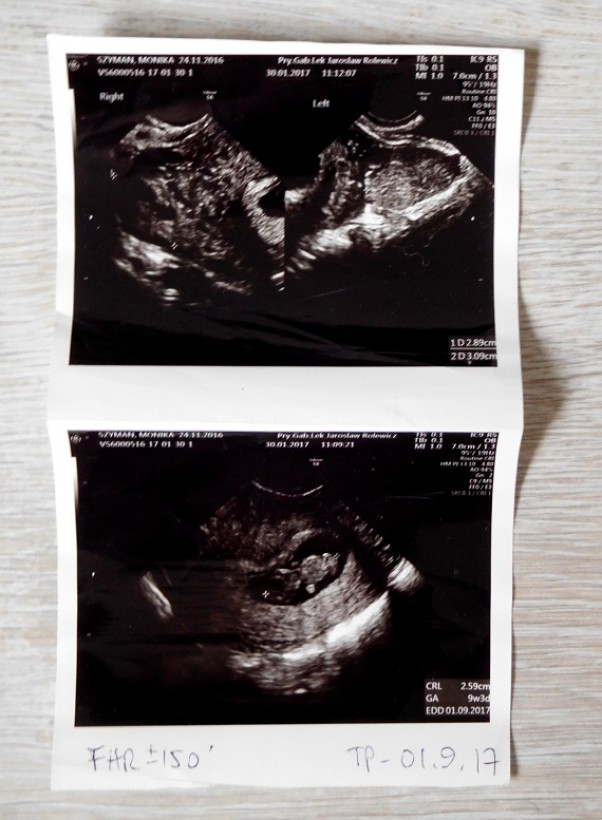

Drugie USG

To już drugie Usg robione 30.01,ale dopiero dziś mam chwilę aby je opisać :) Maluszek był wtedy w 9 tyg i miał 2,59 cm <3 a już machał rączkami i kręcił pupką hihi. Kolejne usg będzie w 15 tygodniu, już się nie mogę doczekać. Kto patrzy na to zdjęcie to mało co widzi ale ja widzę wszystko, główkę, brzuszek, rączki i mini nóżki, moje maleństwo :*